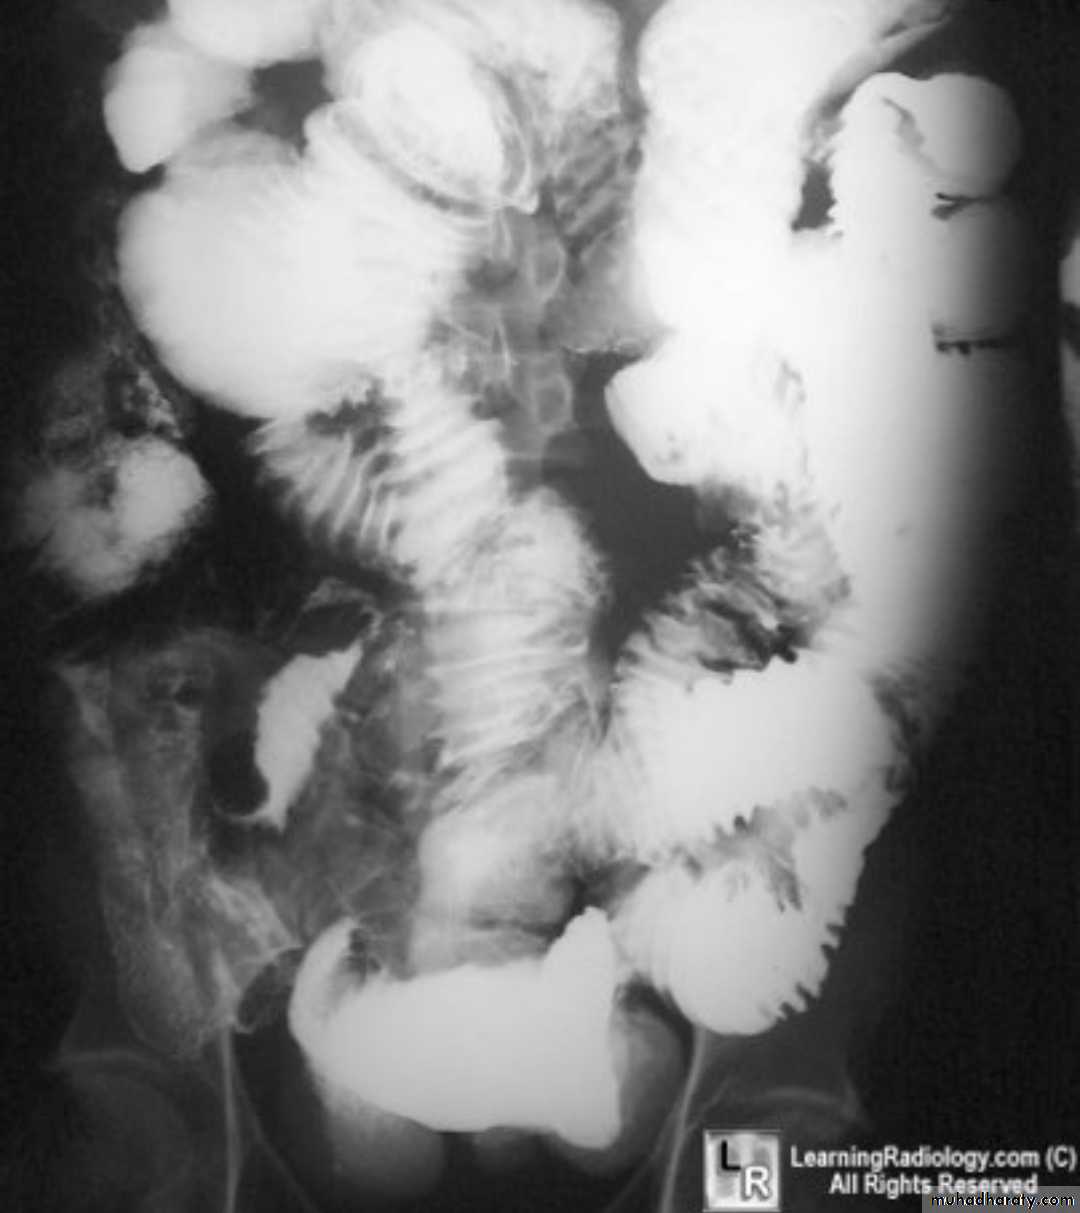

Barium small bowel follow-throughfindings of CD

Multiple mucosal ulcers aphthous ulcerslongitudinal fissures

Multiple skip lesions

when severe leads to cobblestone appearance

may lead to sinus tracts and fistulae

widely separated loops of bowel due to fibro-fatty proliferation

thickened folds due to edema

Pseudo diverticula formation: due to contraction at the site of ulcer with ballooning of the opposite site